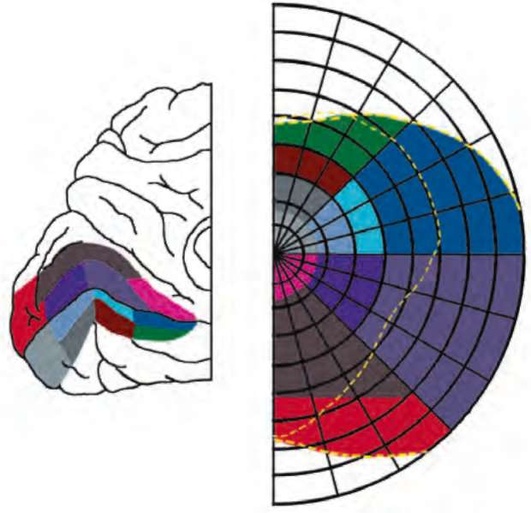

Рис. 2.9. Сетчатка и зрительная кора. Зрительная информация, получаемая глиозными клетками сетчатки, передается первичной зрительной коре (поле 17 по Бродманну), там она распределяется в соответствии с локализацией ее источников в сетчатке